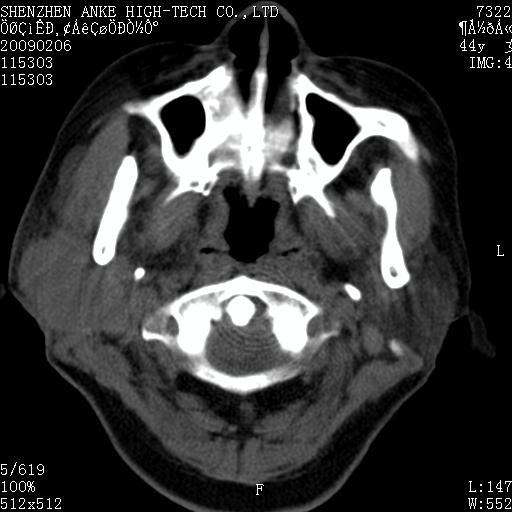

标题: CT17977:女,44岁,右侧颌部包块1年,右侧面瘫2月。 [打印本页]

患者:女,44岁,右侧颌部包块1年,右侧面瘫2月。

考虑右侧腮腺混合瘤可能性大

考虑右侧腮腺混合瘤;不排除腮腺癌。

右侧腮腺肿瘤,良恶性难定。